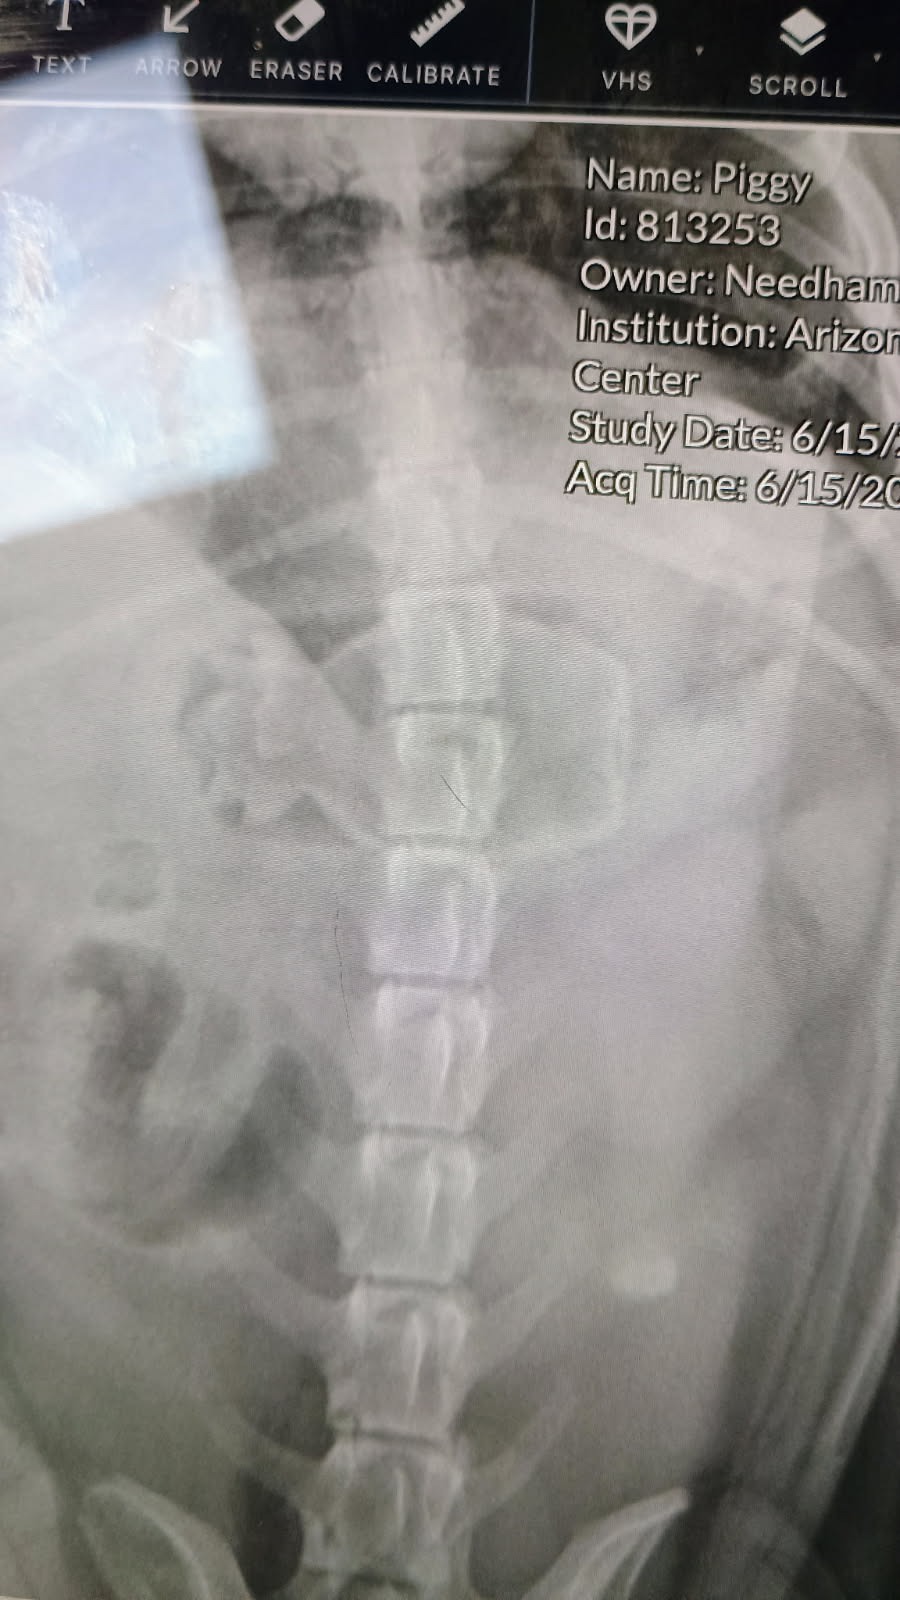

Anyone who knows us knows how much we love our Piggy. She loves to be the center of attention and is one of the family. Unfortunately, she got a hold of a small squeaky toy and swallowed it. We have done everything we possibly can and have now had to resort to seeking professional vet care. They have told us our best option is to have it removed by scope. This procedure is not within our funds. I am hoping that with the love and help of our family and friends, we can raise the funds to get her help before it causes more harm. Any amount is appreciated in this time of need to save our Piggy.